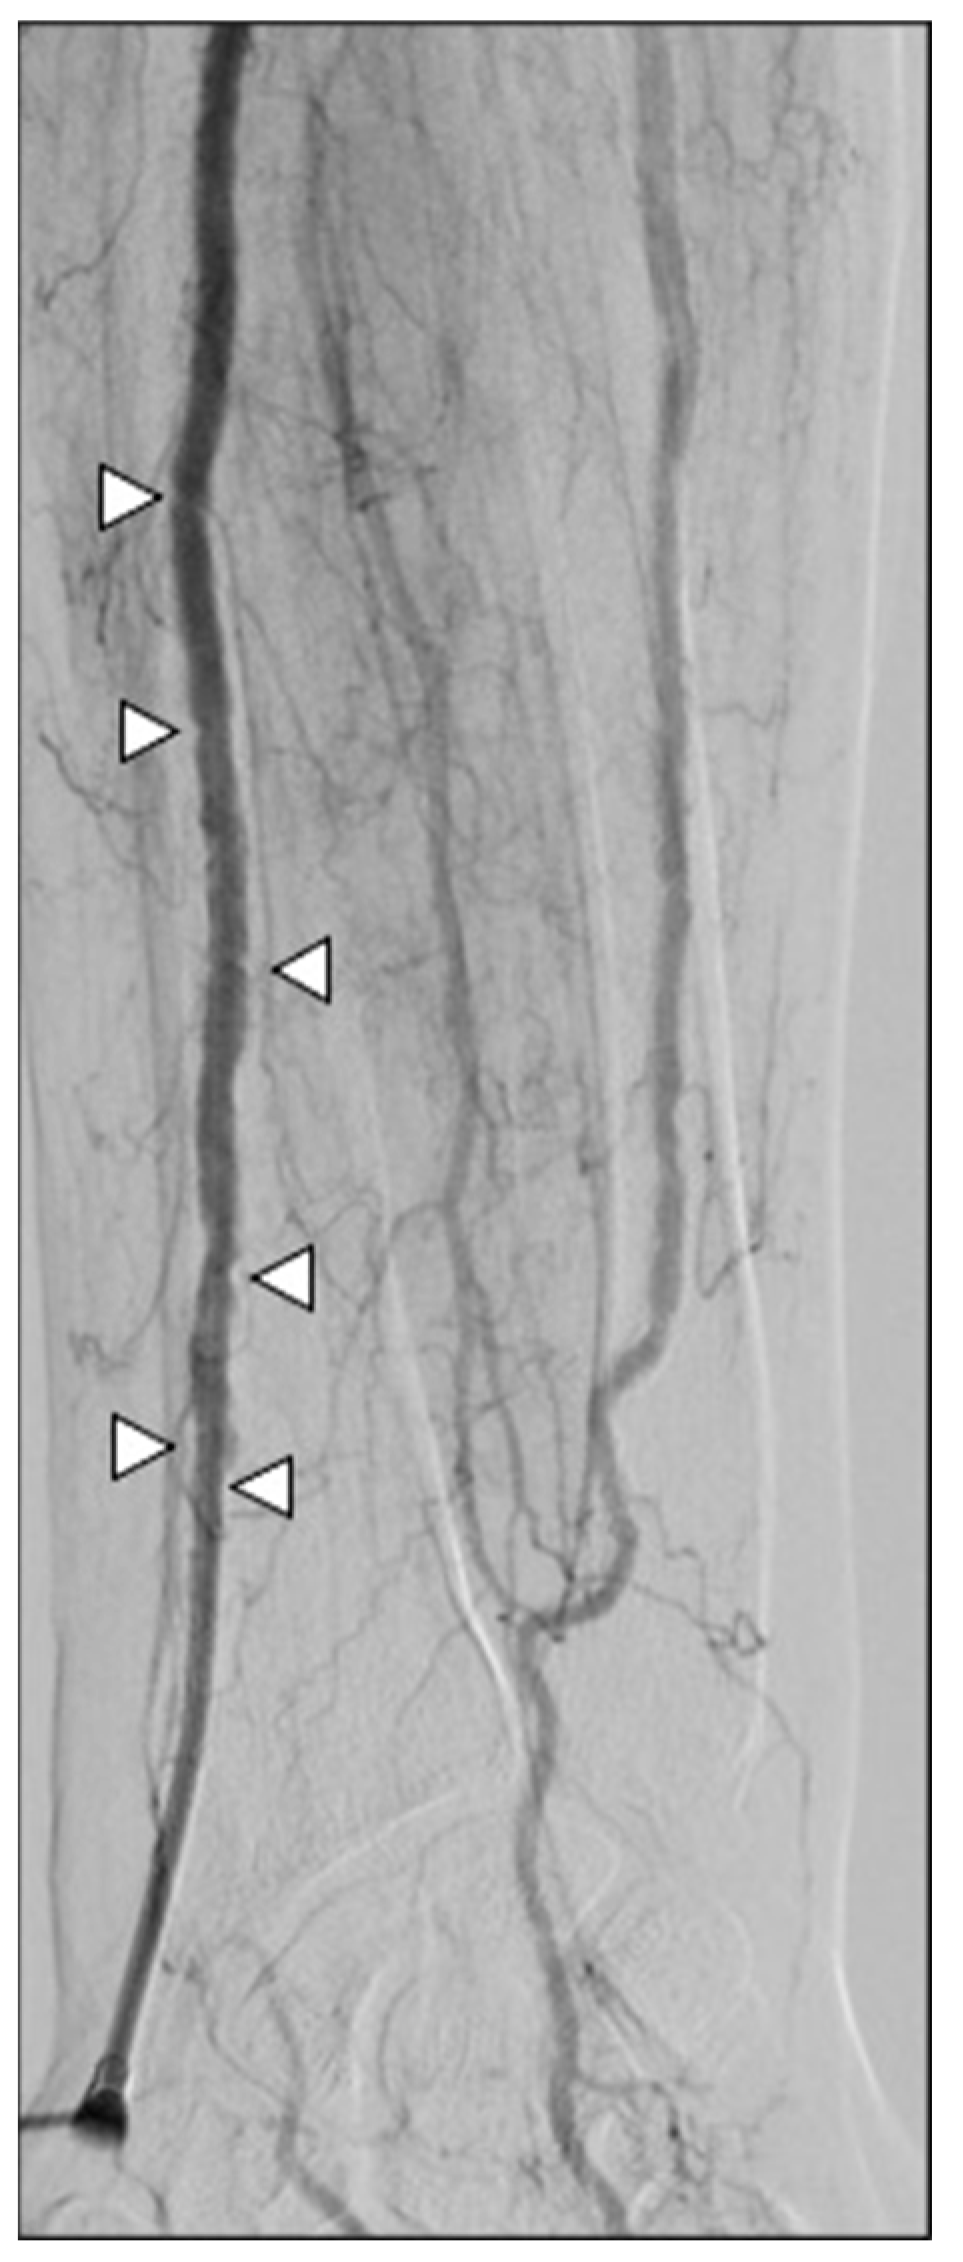

A 5Fr 125 cm diagnostic catheter (Multipurpose or HeadHunter tip) was advanced on a .035″ 260 cm J tip hydrophilic guidewire under roadmap guidance by looping the guidewire tip to skip radial/brachial branches; once the aortic arch was reached, a 45° left anterior oblique projection was acquired to properly depict the aortic course. If issues occurred in engaging the descending aorta, a switch to a 5Fr Pigtail tip catheter was performed, and the guidewire was advanced, opening the loop of the catheter directed into the descending aorta. The diagnostic catheter was adopted to select the coeliac trunk or the superior mesenteric artery, according to the origin of the hepatic artery. After performing DSA and ConeBeamCT (CBCT) examinations to detect lesions feeders, a 2.4Fr microcatheter (Progreat®, Terumo, Japan) was advanced as distal as possible to the target; chemoembolization was then performed, using the conventional (Lipiodol®, Guerbet, France) or degradable starch microspheres (Embocept®, Pharmacept, Germany) technique and Doxorubicin (50 mg diluted in 5 mL of saline) as chemotherapy.

Figure 5.

Arterial navigation. (A) The J tip of the .035″ hydrophilic guidewire was looped (white arrow) while navigating under fluoroscopy via the right radio-brachial axis in order to avoid collaterals; (B) aortic arch and descending aorta were projected in the 45° left anterior oblique plane to improve vessel route visualization; (C) the 5Fr multipurpose diagnostic catheter was positioned into the coeliac trunk, and the 2.4Fr microcatheter was advanced superselectively to intrahepatic segmental branches (as in this SIRT work-up for a S7 HCC lesion, after coiling of an extrahepatic gastro-epiploic feeder); (D) at the end of the procedure, an inflatable wristband was positioned and inflated with 20 mL of air to close the radial access.